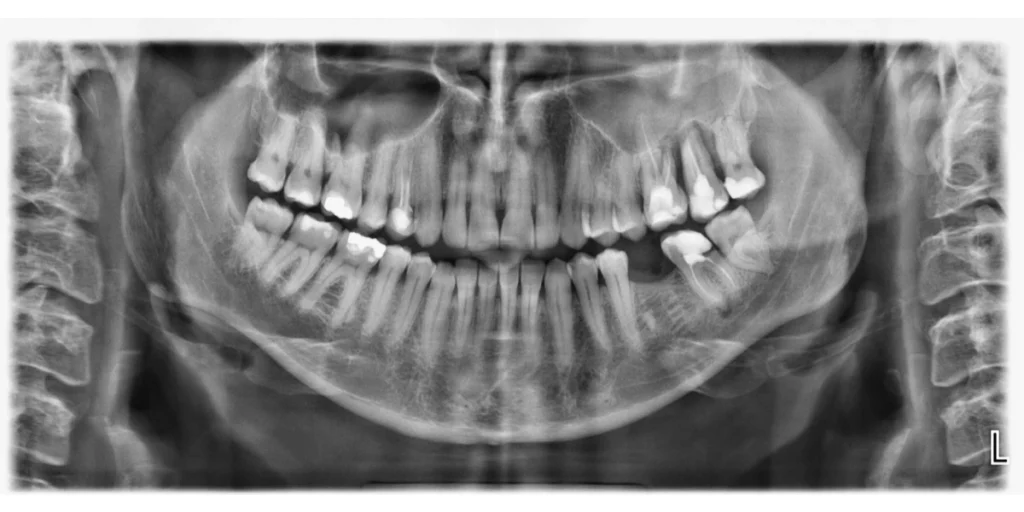

Dentalni radiogram

Retroalveolarni ili “mali” snimak je najčešći tip snimanja zuba i predstavlja ciljani snimak jednog, dva ili tri susedna zuba. Pruža precizne i detaljne informacije o stanju celog zuba:  krunice, njegovog korena i okolnih struktura. Decenijama je nezamenljiv u dentalnoj dijagnostici.

Prednosti digitalnog snimanja u odnosu na tradicionalno:

• Višestruko niža doza zračenja za pacijenta

• Softverska obrada snimka daje bolju rezoluciju i kvalitetniji snimak

• Snimak se u digitalnom formatu može slati na e-mail i viber, narezati na CD ili odštampati na film foliji.